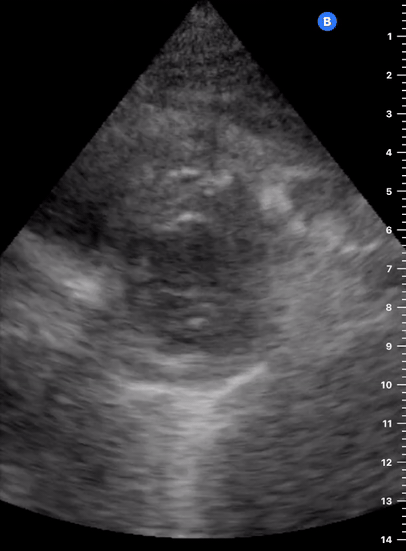

Effusion: is there a pericardial or pleural effusion?

Pericardial effusion is a continuum and can potentially evolve into haemodynamic collapse. Tamponade physiology is detectable earlier with ultrasound than with traditional physical examination, and it has been demonstrated that PoCUS improves mortality in penetrating cardiac trauma. Timely and accurate diagnosis is, therefore, vital.

THE VIEWS

The subxiphoid view is the most reliable for detecting pericardial effusion. Still, it is ideal to obtain different views not to miss a focal effusion as small amounts of fluid can lead to tamponade physiology. Tamponade does not link strictly to the size of the effusion, but correlates more with the speed of onset, causes, and haemodynamic effects.

PITFALLS & PLEURAL EFFUSIONS

A common error is to confuse a pericardial fat pad with effusion. Fatty tissue has a heterogeneous echotexture, moving in coordination with the myocardium, and it cannot be tracked around the heart, especially posteriorly and to the apex. Another pitfall is misinterpreting a pleural effusion as a pericardial effusion. However, they can be differentiated by their relationship to the descending aorta. Pericardial effusion may be seen between the aorta and the LV free wall, whereas pleural effusions are posterior to the descending aorta. Lastly, other causes, namely hypovolaemia and large pleural effusions, can cause RA and RV collapse.

CARDIAC TAMPONADE

Progressively rising pressure translates into evolving tamponade, and this accompanies a series of ultrasound findings:

Initially, the RA collapses during ventricular systole (closed AV valves).

Followed by RV collapse in ventricular diastole (open AV valves).

Ultimately leading to LV collapse.

In addition, the presence of a non-collapsible, plethoric IVC is one of the most sensitive signs of tamponade, and a finding easy to visualise. Conversely, a pericardial effusion in a haemodynamically stable patient with a collapsible IVC is unlikely to represent tamponade.